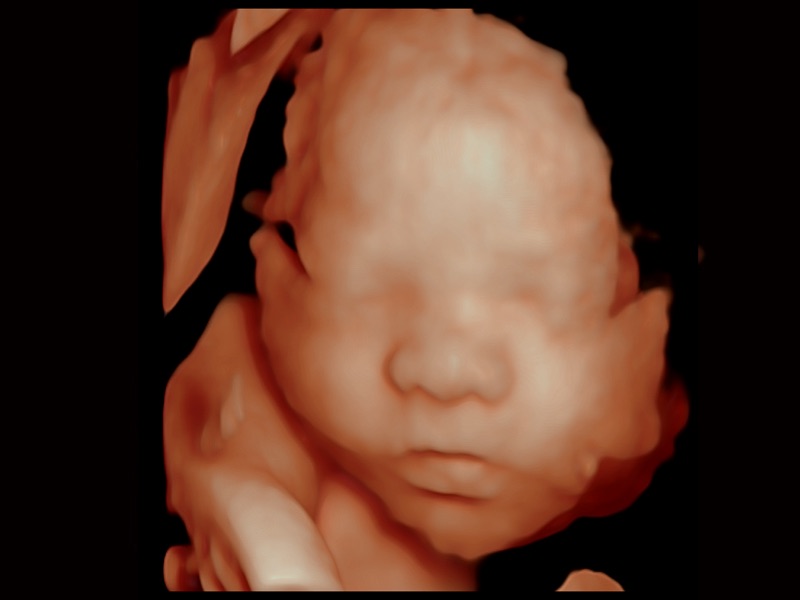

• 光影成像

三维光影成像技术采用新型的渲染方式,增强边缘信息,使得轮显示清晰完整,为临床提供丰富、直观的三维结构,提供临床诊断准确性。

临床图